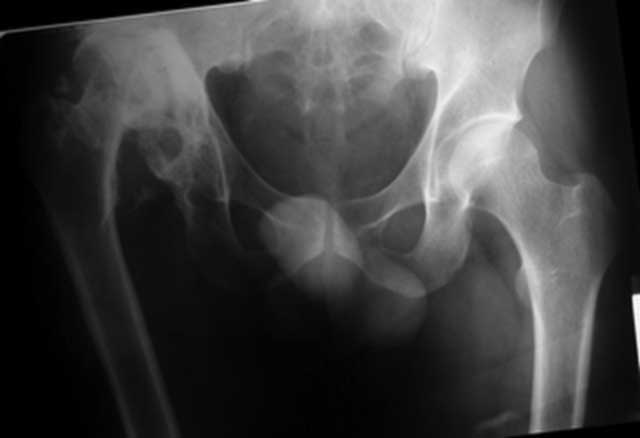

Имя     : вапп.jpg

Url     : http://weborto.net:8080/pipermail/ortho/attachments/20090119/0ccb8dff/attachment-0006.jpg